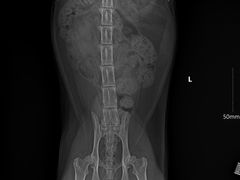

• -艾贝尔宠物诊疗

nyannyan | 23-12-04

报错